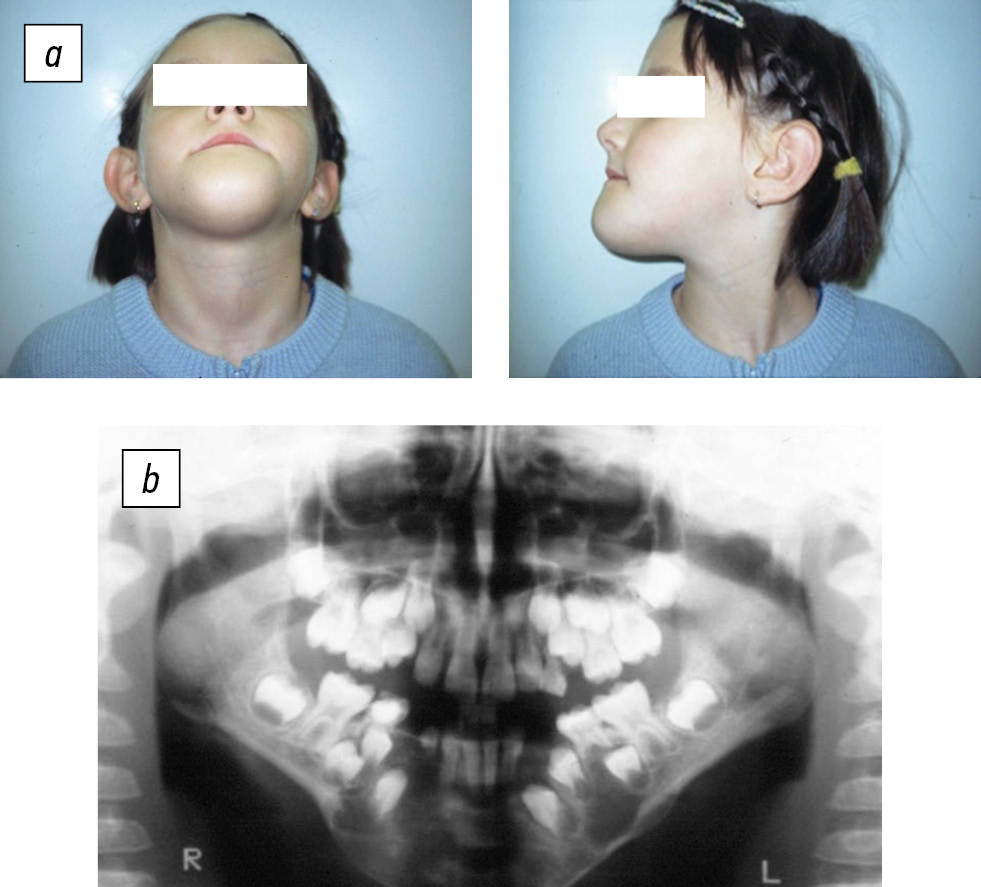

Patient B (5.5 years old) presented to the Pediatric Maxillofacial Surgery Clinic of K.A. Raukhfus Children’s City Hospital No. 19 (St. Petersburg) in 2002 with complaints of impairment of facial contours, pain in the lower jaw, and eating difficulty. Clinical symptoms appeared a few months before the treatment. To clarify the diagnosis, the volume of the bone tissue damage was assessed, surgical treatment was planned, and orthopantomography and computed tomography (CT) of the skull were performed. The main diagnostic method was an extended surgical biopsy under anesthesia, for which the patient was hospitalized for a short time. The study confirmed the preliminary diagnosis of a lower jaw osteoblastoclastoma (Fig. 1).

Fig. 1. Patient B (5.5 years old). Osteoblastoclastoma of the jaw: a, appearance; b, orthopantomogram